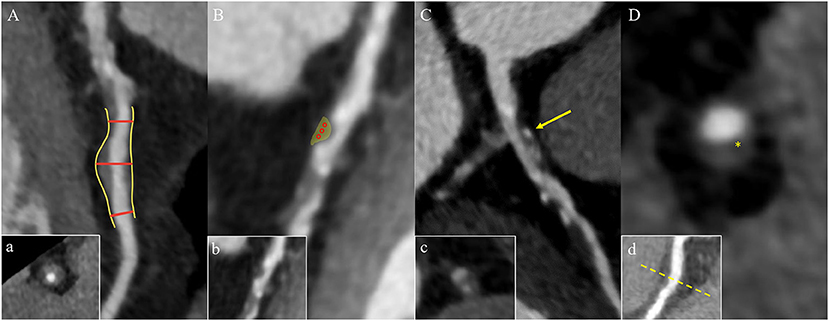

Figure 2. High-risk plaque characteristics on CCTA. (A) Positive remodeling of a non-calcified plaque in the proximal left anterior descending coronary artery. The two short red lines indicate the vessel diameters of the proximal and distal of the plaque (both 1.0 mm), and the long red line indicates the maximum vessel diameter in the middle of the plaque (1.6 mm). The remodeling index is 1.6. Picture a is the cross section of picture (A). (B) A low-attenuation plaque (yellow area) in the mid segment of the left anterior descending coronary artery with a mean CT attenuation value of 21 HU in the three regions of interest (red circles). Picture b is the original picture (B). (C) Spotty calcification of a partially calcified plaque surrounded by non-calcified components in the proximal left anterior descending coronary artery with a diameter <3 mm in all directions (yellow arrow). Picture c is the cross section of picture (C). (D) A napkin-ring sign plaque in the proximal right coronary artery. The yellow star shows the central area of the plaque with a low HU close to the lumen, which is surrounded by the peripheral edge of higher CT attenuation. Picture d is the multiplanar reconstructed image of picture (D). CCTA, coronary computed tomography angiography; HU, Hounsfield units.

Clinically, coronary artery remodeling refers to be the compensatory changes of cross-sectional area and structure of coronary artery in the progression of coronary atherosclerosis. In pathological findings, the lumen of some coronary arteries was found to be increased during atherogenesis in autopsy (36). For in vivo detection of coronary artery, IVUS examination confirmed that the cross-sectional area of the vessel at the atherosclerotic site was significantly larger than that at the proximal reference segment, then the concept of positive remodeling was proposed which refers to the compensatory increase of vessel wall when atherosclerotic plaque volume increases continuously, thus maintaining the effective area in the lumen (37). While on CT, the outer vessel wall dimension could be measured. The remodeling index (RI) is calculated by dividing the vessel cross-sectional area/diameter of the largest stenosis (or maximum vessel area/diameter) by the average cross-sectional area/diameter of the proximal and distal reference segments (7, 38, 39) (Figure 2Aa). At present, positive remodeling is generally defined as RI ≥ 1.1 in CCTA (8, 40, 41), while some researchers prefer other cut-off point (42, 43). In addition, automatic software makes it easier to quantify the RI (44).

Low Attenuation

The composition of plaques can be reflected by CT attenuation value, with the highest CT attenuation value for calcification, followed by fibrous tissue, and the lowest CT value for lipid. Low-attenuation plaques refer to those with the lowest CT attenuation value and the most easily ruptured lipid composition (a lipid-rich necrotic core), which is defined as mean attenuation <30 Hounsfield units (HU) of at least three regions of interest (ROIs) in general (39, 45) (Figure 2Bb). However, the CT attenuation value of lipid plaques overlaps with that of fibrous plaques, so it is difficult to distinguish the plaques only by CT attenuation value alone. In addition, the CT value of plaques is affected by many factors, such as contrast agent, plaque volume, slice thickness, tube voltage, and so on. Therefore, the current research mainly relies on special procedures to identify which plaque is low-attenuation (7, 45).

Spotty Calcification

Spotty calcification is the initial state of calcification. Since calcification is one of the consequences of local inflammation, spotty calcification may indicate active local inflammation. Mechanical stimulation on fibrous cap caused by spotty calcification and local inflammation may lead to the plaque with spotty calcification easy to rupture, thereby accelerating disease progression (46–48). Therefore, spotty calcification is considered to be one of the characteristics of high-risk plaques. In CCTA, spotty calcification is generally manifested as calcification in plaques with a density of more than 130 HU and a diameter of <3 mm surrounded by non-calcified components (42, 49, 50) (Figure 2Cc). However, only calcification more than 0.5 mm in diameter is visible on CT, so nearly two-thirds of the calcifications cannot be recognized on CT (51, 52).

Napkin-Ring Sign

The napkin ring sign is a qualitative plaque feature that can be defined by the presence of two features on the cross section of non-calcified plaques: the low-attenuation central area obviously contacting with the coronary artery lumen and the annular high attenuation plaque tissue surrounding the central area (7, 34) (Figure 2Dd). Histologically, the low-density area corresponds to the large necrotic nucleus, while the “annular” outer area is associated with fibrous tissue. The necrotic core area in plaque with the napkin-ring sign may be more than twice that without napkin ring sign (1.10 vs. 0.46 mm2) (53) corresponding to some studies' indications that a necrotic core area >1 mm2 when plaque is prone to rupture (14). The density of the ring is greater than that of the inner core but <130 HU in CT scans. Currently, the napkin-ring sign is considered to be a special CT feature of plaque with a large necrotic core, and it is a reliable marker of plaque instability (7, 14).